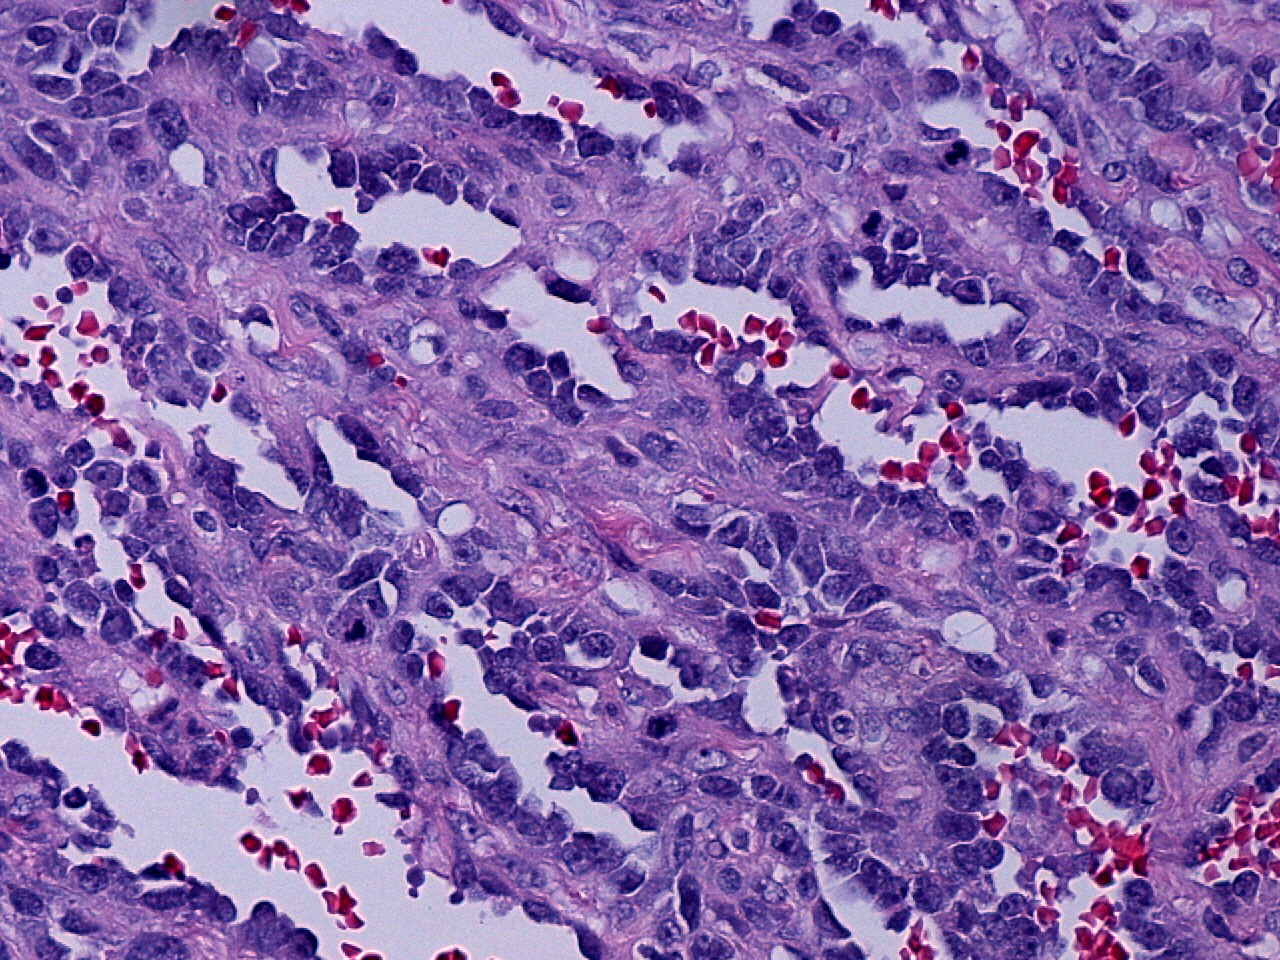

Angiosarcoma is a rare and aggressive, malignant neoplasm of endothelial-cell origin. A primary angiosarcoma originating in the testicle is extremely rare, with only five previous cases reported in the current literature. We report a case of primary, pure angiosarcoma of the testis in a 63-year-old patient with no history of previous chemotherapy or radiation therapy. By histology, the tumor was a high-grade spindle cell neoplasm, arranged in sheets and poorly-formed vascular channels. The tumor cells were positive for vascular markers (CD31, CD34) by immunohistochemical staining. No evidence of a germ cell component was seen by morphology, immunohistochemistry, or molecular genetic studies. This finding is unique in that it is one of only three reported cases of primary angiosarcomas of the testicle without a germ cell precursor or component.